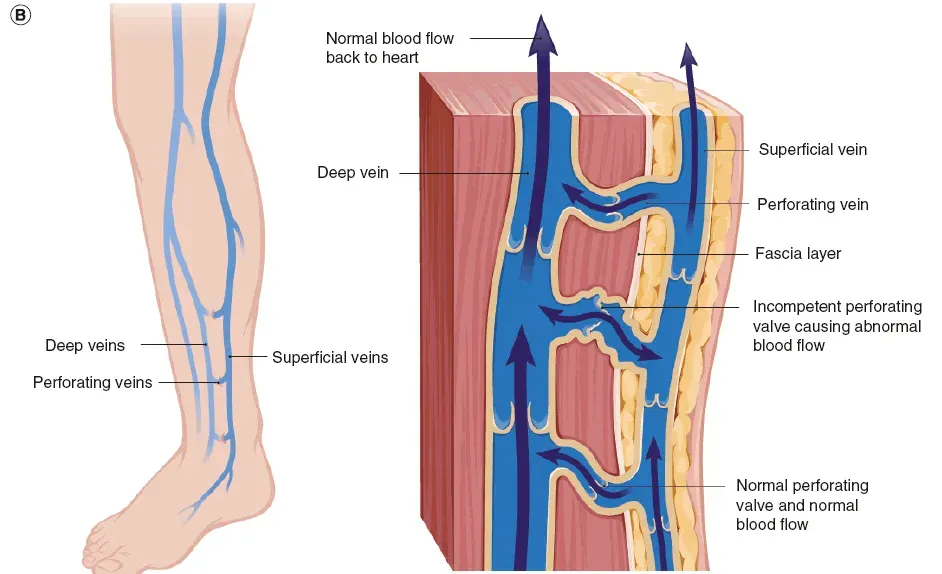

TIPS: 下肢静脉层级网络

覆盖隐静脉表面的筋膜称为“隐筋膜”,其与深筋膜之间的间隙称为“隐筋膜室”。下肢静脉至此刻划分为三个解剖层次,即:深层(深筋膜之下);筋膜间层(深筋膜与隐筋膜之间,即皮下深层)和皮下层(皮肤与隐筋膜之间,即皮下浅层)。

Franceschi和Zamboni将其称为解剖筋膜室 (anatomical compartment, AC),三层分别为AC1、AC2和AC3,其内走行的静脉分别为N1(深静脉系统)、N2(大隐静脉系统)和N3(大隐静脉属支)。